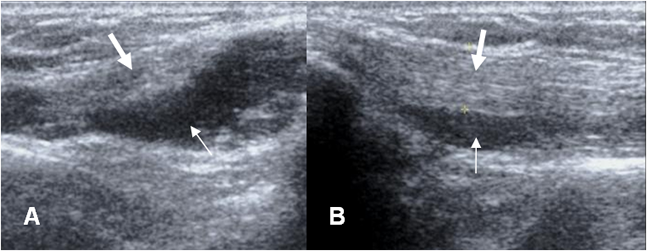

Fig 53 A. Tendinitis tríceps.

A: Ecografía transversal y B: Ecografía longitudinal. Presencia de líquido (Flechas delgadas) rodeando el tendón del tríceps (Flechas gruesas), por tendinitis.